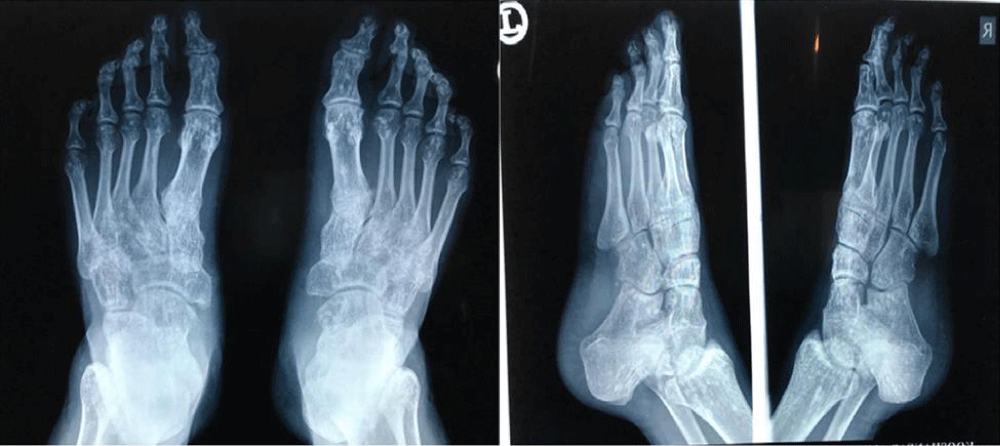

X-ray studies of feet, ankles, hands, wrists, and pelvis revealed the existence of multifocal clusters of small, round to oval, well-defined border, sclerotic lesions located along the proximal and distal epiphysis of joints, at bilateral tarsal joints in lisfranc and Chopart, MTP (metatarsophalangeal), PIP (proximal interphalangeal), DIP (distal interphalangeal) of both feet, both hips, wrists, MCP (metacarpophalangeal), PIP and DIP joints of both hands. The morphology of these lesions noticed on X-rays was identical to those seen in osteopoikilosis. All bones were free of any cortical erosion or periosteal reaction (Figures 1,2).

Figure 2: Anteroposterior (AP) and Oblique view radiography of both feet.